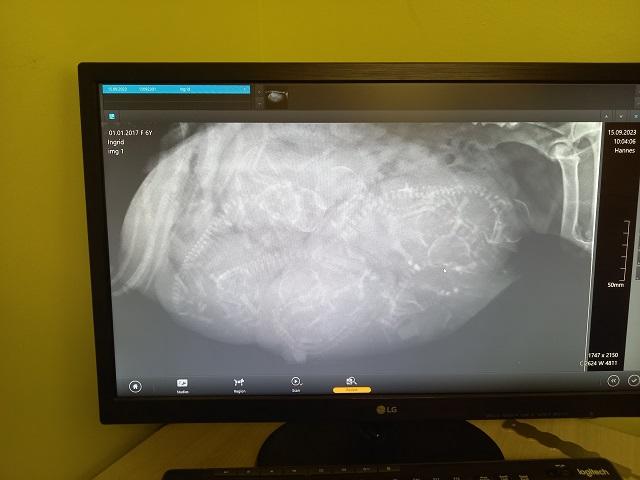

Röntkeni-ruumis said soovijad selga proovida spetsiaalset riietust. Läbi arvutiekraani nägime kassi jalaluumurdu ja saime üle lugeda emase koera veel poegimata kutsikad.